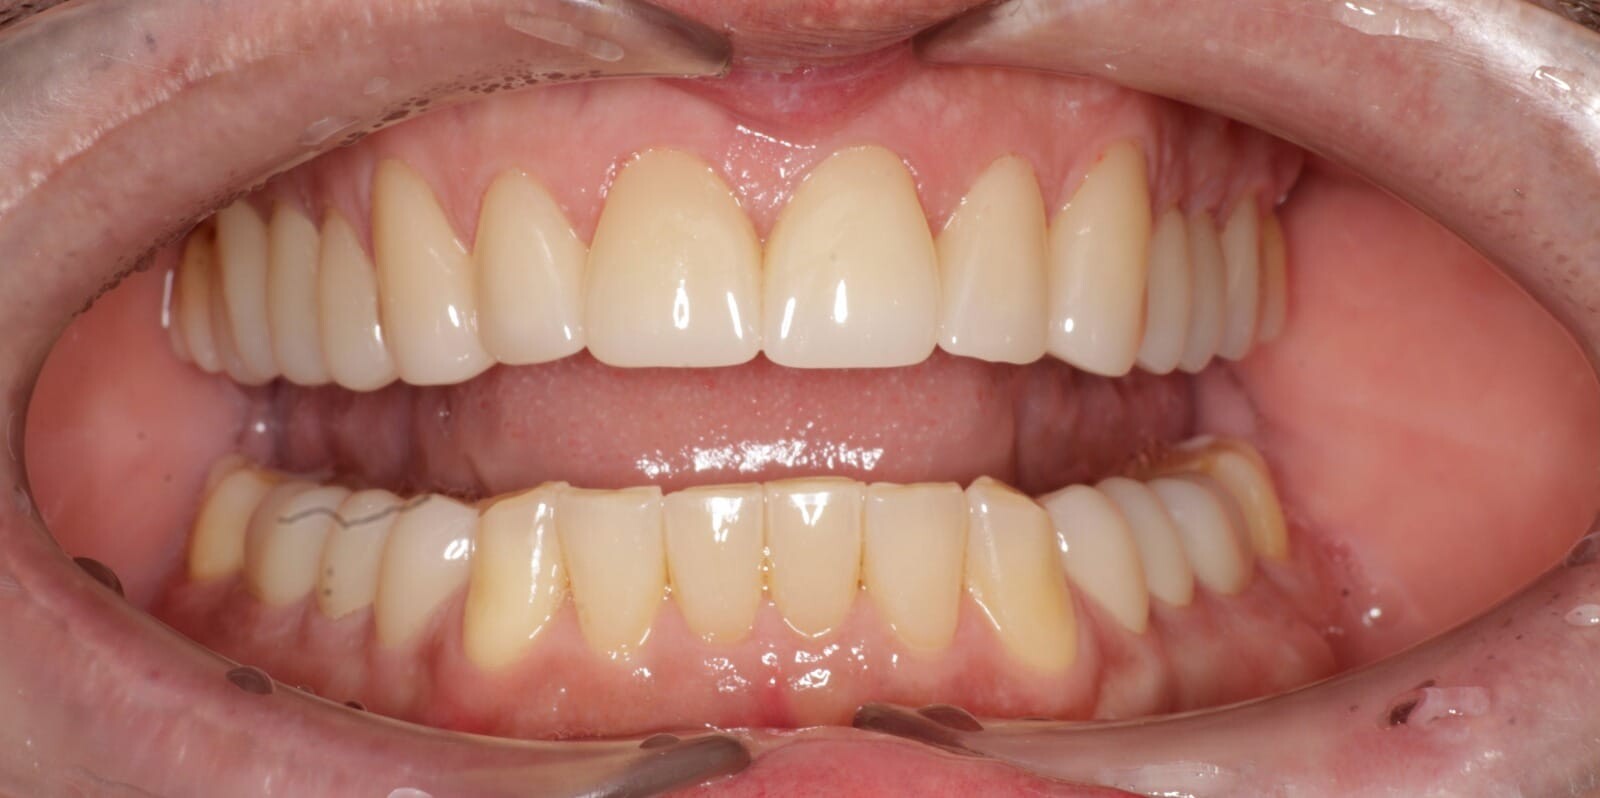

Fotografía digital intraoral de una reconstrucción de zirconia.

Fotografía intraoral a boca cerrada de una reconstrucción de zirconia de todas las piezas posteriores y de las áreas posteriores inferiores.